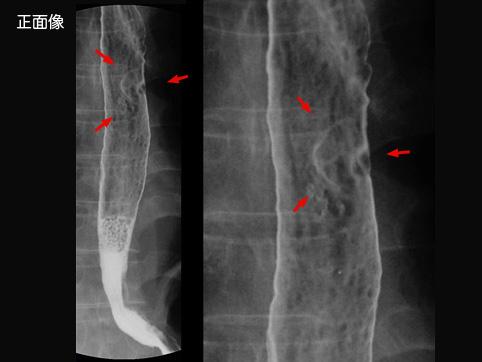

표재상피하 종괴형(0-Isep형)

점막하 조직층(sm층)에 다량으로 침윤한 0-Isep형의 식도암

악성 상피성종양/편평상피암

식도/중

X-P

20~24

sm